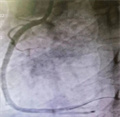

急诊科李博医师接诊后,立即启动胸痛绿色通道,心内科钱俊医师评估后,考虑患者在急诊介入时间窗内,立刻告知了家属病情的危险,急需紧急手术。在为患者生命护航的“绿色通道”,各科室通力合作,导管室人员迅速就位,立即投入到紧张的救治当中。途中患者出现二度房室传导阻滞,急诊上台约十分钟后出现心率、血压下降,病情十分凶险,心血管内科副主任医师吴义权、主治医师夏秋旺沉着冷静应对、默契协作,快速开通血管、稳定血压和心率,成功为堵塞的血管实现再通,使患者脱离了危险。

该患者D-to-B(进门到导丝通过)时间仅用了51分钟,远远低于胸痛中心要求90分钟,这充分展现了我院胸痛救团队的高效协作和救治能力。我院胸痛中心自启动建设以来,严格按照创建标准,以心血管内科为主,多学科联动,畅通了胸痛病人抢救的绿色通道,让上百名胸痛急危重症患者第一时间得到及时和规范的诊断治疗。